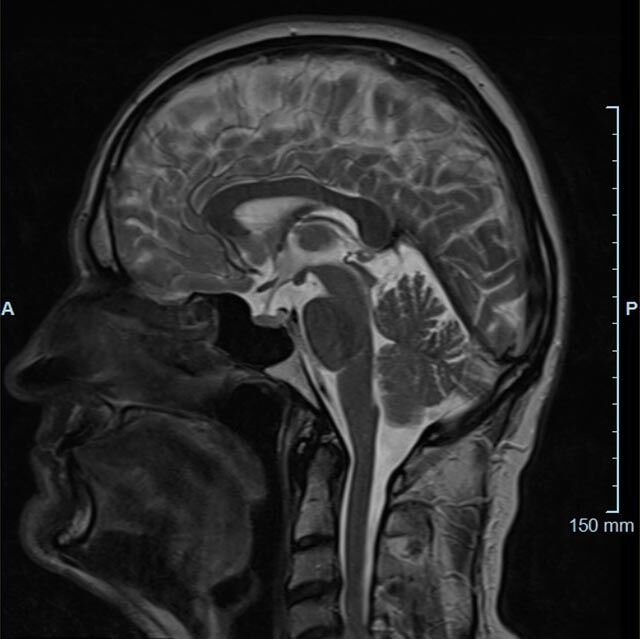

Kopf/Hals

Kopf

• akute Schlaganfalldiagnostik und chronische Durchblutungsstörungen

• entzündliche Prozesse des Gehirns oder der Gesichtsweichteile

• Tumore, ggf. mit Spektroskopie

• Abklärung Schwindel, zentrale Sehstörung, Kopfschmerz

• Metastasenverdacht

• Multiple Sklerose

• Abklärung Hirnnerven, Schädelbasis inkl. Hypophyse

• Abklärung Kleinhirn, Hirnstamm, Halsmark

• intrakranielle Gefäße (Abklärung Verschluss, Stenose, Aneurysma)

• Halsgefäße zur Therapieplanung (z.B. Stent, Operation)